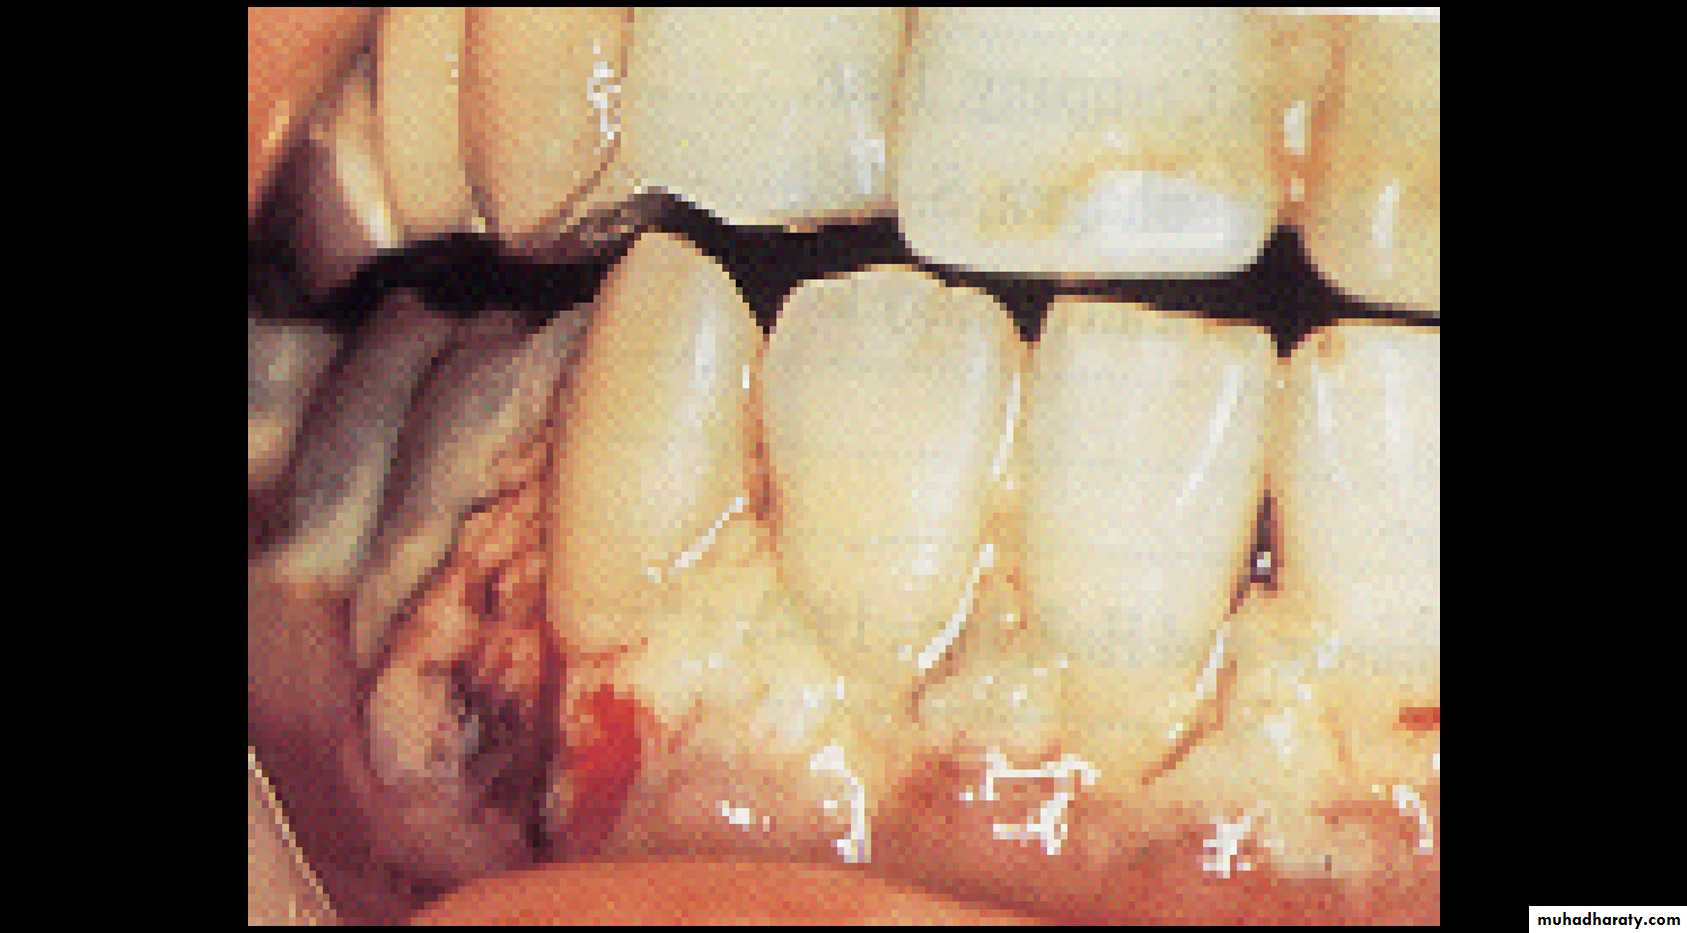

• Gram-negative, strictly anaerobic, cigar-shaped bacilli with pointed ends ( Cells often have a central swelling.• A Gram-stained smear of deep gingival debris obtained from a lesion of acute ulcerative gingivitis is a

• These, together with the clinical picture, confirm a clinical diagnosis of acute ulcerative gingivitis

acute (necrotizing) ulcerative gingivitis or trench mouth (Vincent’s angina, an ulcerative tonsillitis causing tissue necrosis, often due to extension of acute ulcerative gingivitis

A Gram-stained smear obtained from deep gingival plaque of a

patient with acute ulcerative gingivitis showing the fusospirochaetal complex. Note: the large cells are polymorphs.Antibiotic sensitivity and prevention